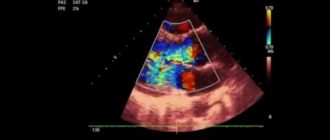

Врожденные пороки сердца (ВПС) Дефекты сердца могут встречаться изолированно или в сочетании друг с

Недостаточность аортального клапана — 1, 2, 3 степени, причины, симптомы, лечение, прогноз, МКБ-10, у